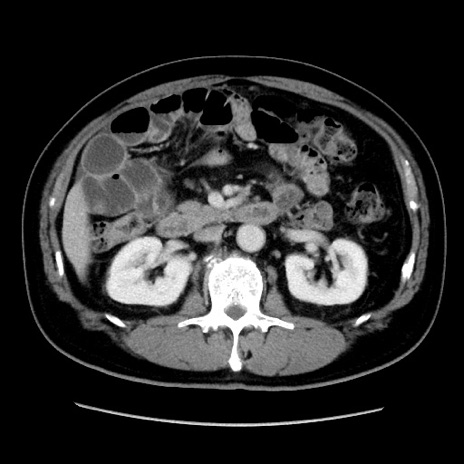

症例16(横断像)

【症例】 70歳代男性

【主訴】 腹痛、嘔吐

【現病歴】 約1ヶ月前より間欠的に腹痛と嘔吐あり、当院消化器内科を受診したところCTで多発する肝臓のLDAを指摘され、精査中であった。以降は消化器症状は安定していたが、2日前より嘔気と腹痛があり、同日より排便・排ガスが消失した。改善認めず、 本日、救急外来を受診した。

【既往歴】 大腸ポリープ切除後。

【身体所見】意識清明・会話良好、BT 36.3℃、BP 127/80mmHg、 P 80bpm、腹部:膨満あり、平坦・軟、上腹部正中および下腹部正中に圧痛あり、反跳痛なし、筋性防御なし。

【データ】WBC 7200、CRP 0.77